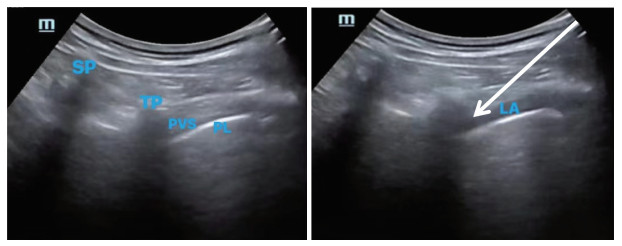

神经阻滞:患者全麻后取侧卧位。由不知分组情况的麻醉医师在超声(SonoSite便携式彩色超声诊断系统,M-Turbo,苏州富士胶片映像机器有限公司)引导下实施T4~T8胸椎旁阻滞。穿刺区消毒铺巾后,自第12肋向头侧移动探头定位横突间隙,识别横突、胸膜及肋横突韧带,于胸膜浅层、横突外侧可见三角形低回声区,即胸椎旁间隙。把探头向尾侧平移,直至横突声像消失即至横突间隙平面,该水平胸椎旁间隙较显著,依次行T4~T8间椎旁神经阻滞,每间隙注射8 mL药液。T1组给予0.4%盐酸罗哌卡因(40 mL),T2组给予0.3 μg/kg右美托咪定+0.4%盐酸罗哌卡因(40 mL),T3组给予8 mg地塞米松+0.4%盐酸罗哌卡因(40 mL)。注药后超声下观察药液扩散及胸膜下压确认阻滞效果,超声下图像见图 1。

|

| SP, spinous process; TP, transverse process; PVS, paravertebral space; PL, pleura; LA, local anesthetic. The arrow shows the route of needle insertion. 图 1 椎旁间隙超声下图像 Fig.1 Ultrasound image of the paravertebral space |